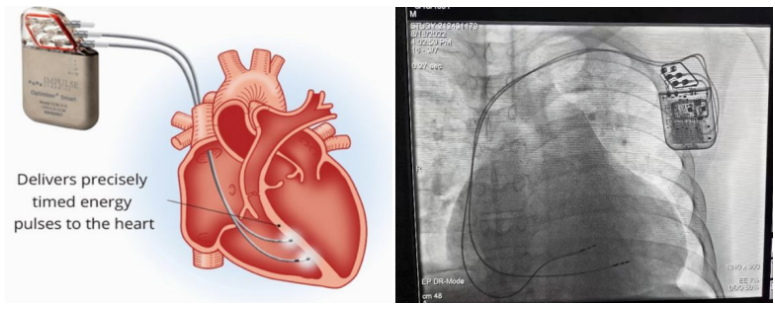

①植入式心臟復(fù)律除顫器

Implantable Cardioverter Defibrillator,ICD

植入式心臟復(fù)律除顫器是一種具有除顫功能的高級起搏器,是一種體積小、能植入患者胸部皮下組織的醫(yī)療設(shè)備。慢性心衰患者易發(fā)生室性心動過速或心室顫動,導(dǎo)致心源性猝死(SCD)。ICD 則能在幾秒內(nèi)自動識別并治療快速室性心律失常,通過低能量心臟轉(zhuǎn)復(fù)和高能量除顫等功能,顯著降低惡性室性心律失常引起的猝死風險??杉皶r自動為患者轉(zhuǎn)復(fù)心律,通俗地說就是裝在體內(nèi)的自動除顫儀。

國內(nèi)研發(fā)企業(yè):無雙醫(yī)療、邁瑞、魚躍、久心、微創(chuàng)、維偉思、麥邦等